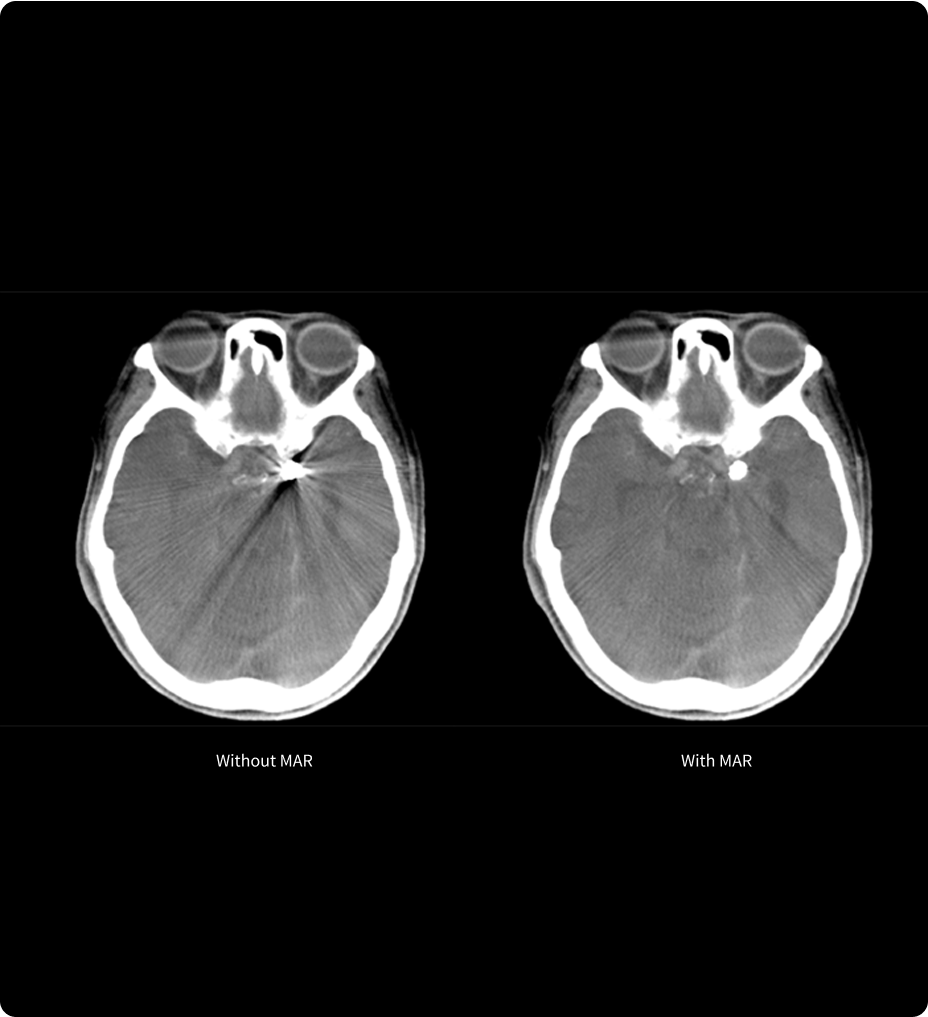

Diagnóstico más fundamentado con mayor inteligencia de imágenes mediante Smart MAR

Smart MAR se ha diseñado para mostrar detalles anatómicos que se ven oscurecidos a causa de los artefactos metálicos, de modo que los profesionales de la salud pueden usar exploraciones de TC, diagnosticar enfermedades y definir objetivos y órganos críticos con mayor confianza.